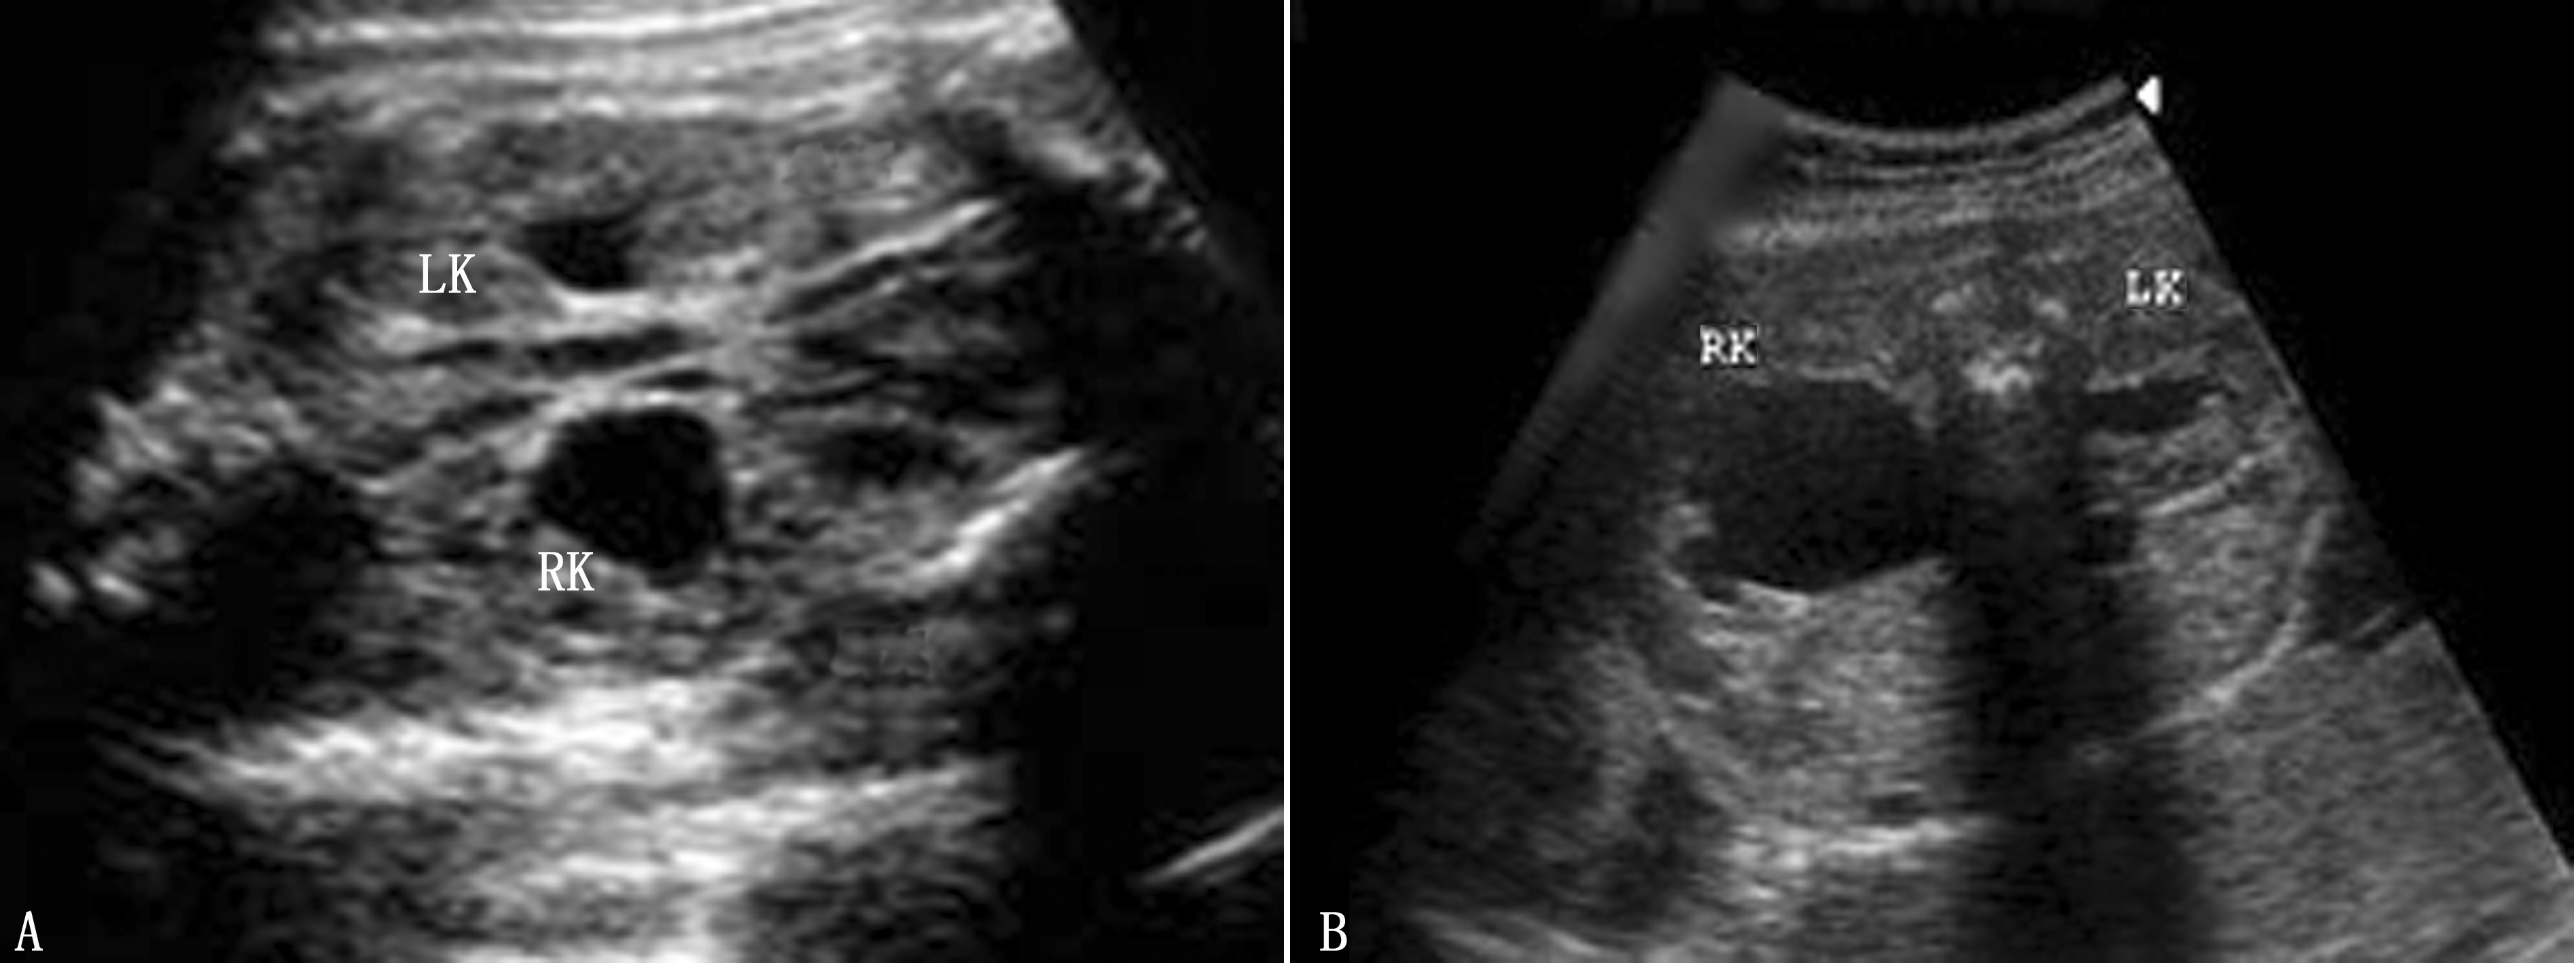

超声显像检查显示胎儿肾盂扩张是诊断胎儿肾积水的依据(图1,2)。美国胎儿泌尿外科学会(SFU)制定的分度方法(排除膀胱输尿管反流所致的肾积水),分为5级:

图1 20周(A)及22周(B)胎儿双侧肾积水,右肾明显